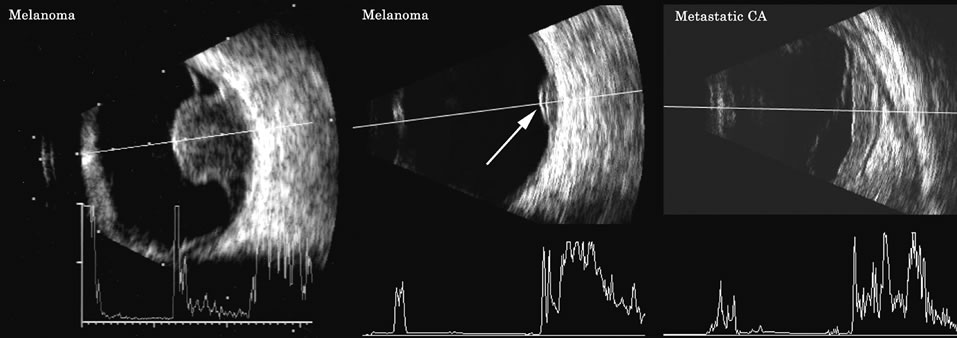

Malignant melanoma varies in its ultrasound presentation from a relatively homogeneous to heterogenous lesion on B-scan. The typical uveal melanoma absorbs sound so that the posterior section is relatively less echoic than the anterior aspect, producing a gradually decreasing amplitude, often to baseline on the A-scan (Fig. 21).

Melanomas also have varying amounts of melanin, a highly acoustically reflective pigment. As noted, melanomas characteristically show high reflectivity anteriorly, with decreasing reflectance as the sound traverses the tissue. This produces the decreasing amplitude posteriorly in the tumor seen on A-scan and gray-scale B-scan. This effect often enhances the anterior scleral boundary. The posterior tumor border is thus measured as the first “rising” echo from the tumor decline, and it is most easily seen and accurately identified on B-scan.27 Metastatic carcinoma is more heterogeneous, producing a more uniform A-scan amplitude of roughly 50% to 80% of the “scleral” echo amplitude (see below) behind the tumor (Fig. 22). Hemangioma is a very highly reflective tumor with high amplitude all the way through the tumor of 80% to 100% of scleral echo amplitude (Fig. 23). The differentiation of tumor tissues is made possible by differences in cellular organization and concentration.29 Acoustically, these are termed as differences in backscattering properties.30–32 A homogeneous solid tissue, such as the lens or the optic nerve, may present few or no echogenic discontinuities and thus appear anechoic and cyst-like. (An echogenic discontinuity is technically an acoustic impedance mismatch in which the acoustic impedance is the product of the density and the speed of sound in each tissue.) A fluid–smooth tissue boundary has a high mismatch or discontinuity and thus produces a high-amplitude echo. A hemangioma with alternating blood- and tissue-lined sacs thus produces a solid-appearing tissue with high-amplitude echoes seen at all depths of the tissue. A metastatic tumor is nearly always a very heterogeneous tissue with randomly organized clumps of similar cells bounded by strands of vessels, necrotic areas, and connective tissue, thus producing a pattern of moderately high-amplitude sustained echoes. To provide a meaningful, reproducible standard of comparison, we use the scleral echo—that is, an echo behind the tumor—for comparison. We believe that the scleral echo generally is highest at the posterior sclera–Tenon's boundary; whereas Ossoinig has stated that the high amplitude echo is at the anterior scleral boundary.28,33 This school (standardized echography) also recommends a tissue velocity for melanoma of 1550 m/sec34,35 compared with the value of 1660 m/sec that we recommend. These differences can produce significant variations in measurement of tumor height, depending on the interpretive methodology used. The velocity of 1550 m/sec gives a smaller tumor height than that of 1660 m/sec, wheras the inclusion of scleral thickness may add 1 to 2 mm to the tumor height when standard echography is used. While this does not affect comparisons of tumor growth, it has a significant bearing on comparisons of data from various investigators.27 On B-scan, the invasion or replacement of the choroid by tumor is of diagnostic importance. Subretinal hemorrhage rests on a smooth curve of the posterior poles; whereas melanoma may replace the choroid, producing an “excavated” pattern.36 A completely dislocated lens can also emulate a tumor but can be differentiated by clinical findings and by having the patient move his or her eye during the examination, which causes lens displacement (Fig. 24).